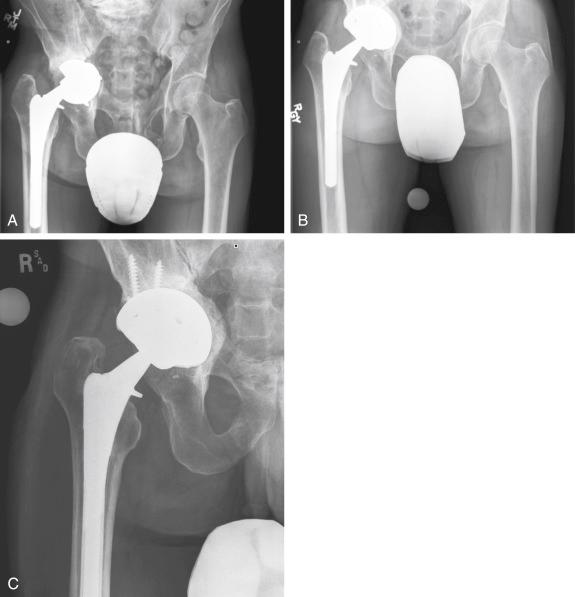

A 51-year-old man presented 2 years after THA with complaints of groin pain during weight bearing. His acetabular component was loose and had migrated medially. He was treated with a larger acetabular component with peripheral fixation and bone grafting ( Fig. 56.2 ).

FIGURE 56.2, A, The anteroposterior radiograph of a 51-year-old man shows failure of the acetabular component and protrusio. B, Intraoperatively, a large medial defect was noticed, but there was sufficient anterior and posterior column for placement of the acetabular component with screw fixation. C, One year postoperatively, the medial bone graft has incorporated and remodeled.